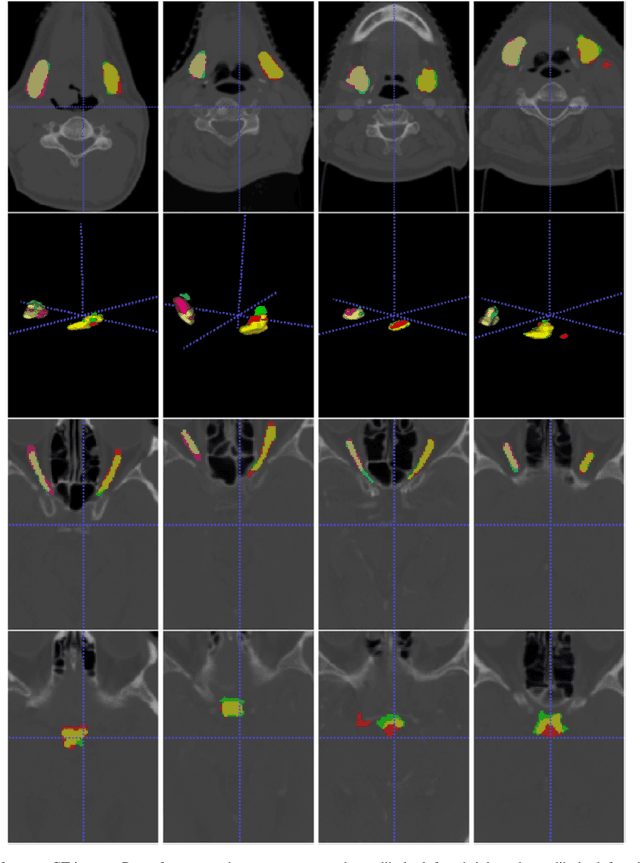

Radiation therapy (RT) is a common treatment for head and neck (HaN) cancer where therapists are often required to manually delineate boundaries of the organs-at-risks (OARs). Automated head and neck anatomical segmentation provides a way to speed up and improve the reproducibility of radiation therapy planning. In this work, we propose the AnatomyNet, an end-to-end and atlas-free three dimensional squeeze-and-excitation U-Net (3D SE U-Net), for fast and fully automated whole-volume HaN anatomical segmentation. There are two main challenges for fully automated HaN OARs segmentation: 1) challenge in segmenting small anatomies (i.e., optic chiasm and optic nerves) occupying only a few slices, and 2) training model with inconsistent data annotations with missing ground truth for some anatomical structures because of different RT planning. We propose the AnatomyNet that has one down-sampling layer with the trade-off between GPU memory and feature representation capacity, and 3D SE residual blocks for effective feature learning to alleviate these challenges. Moreover, we design a hybrid loss function with the Dice loss and the focal loss. The Dice loss is a class level distribution loss that depends less on the number of voxels in the anatomy, and the focal loss is designed to deal with highly unbalanced segmentation. For missing annotations, we propose masked loss and weighted loss for accurate and balanced weights updating in the learning of the AnatomyNet. We collect 261 HaN CT images to train the AnatomyNet for segmenting nine anatomies. Compared to previous state-of-the-art methods for each anatomy from the MICCAI 2015 competition, the AnatomyNet increases Dice similarity coefficient (DSC) by 3.3% on average. The proposed AnatomyNet takes only 0.12 seconds on average to segment a whole-volume HaN CT image of an average dimension of 178x302x225.